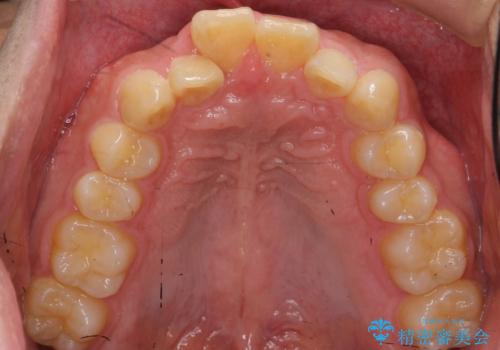

上顎は歯を抜かずに、奥歯を後ろに下げる治療を行っています。

下顎は歯列を拡大して並べました。

歯を抜かずに奥歯を後ろに動かすために、矯正用のミニスクリューを使用しています。

また、過蓋咬合(深いかみ合わせ)で食いしばりがきつく、歯の移動には大変時間がかかりました。